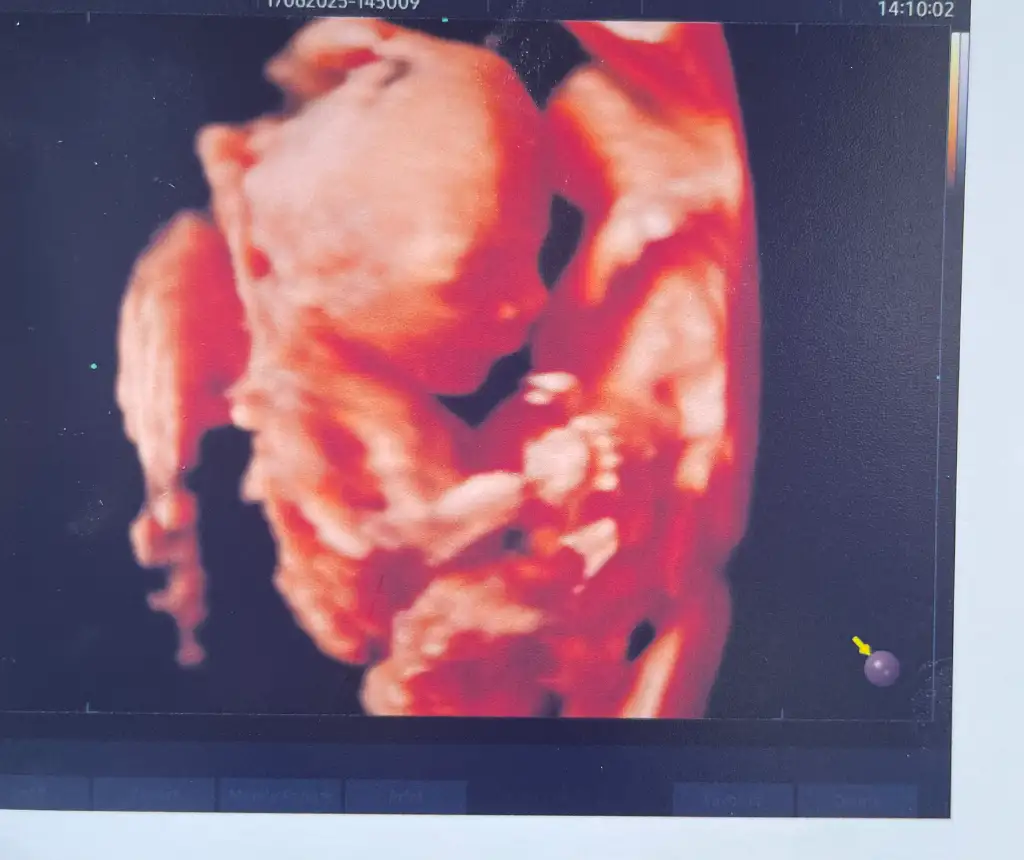

Sağlikla gelsin canimÇok şükür sıkıntı yokmuş hissedememem normalmiş çünkü biraz sakin bi kızım varmış elhamdülillah%100 emin olamamakla beraber büyük ihtimal kız, sen kızın olacak diye düşün dedi